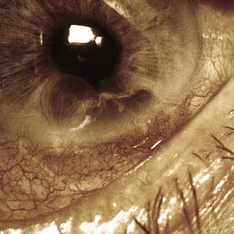

Slide 7-21

Feb 25 2019 by Lancaster Course in Ophthalmology

Squamous cell carcinoma of the conjunctiva may present as an exuberant tumor mass.

Condition/keywords: conjunctiva, tumor